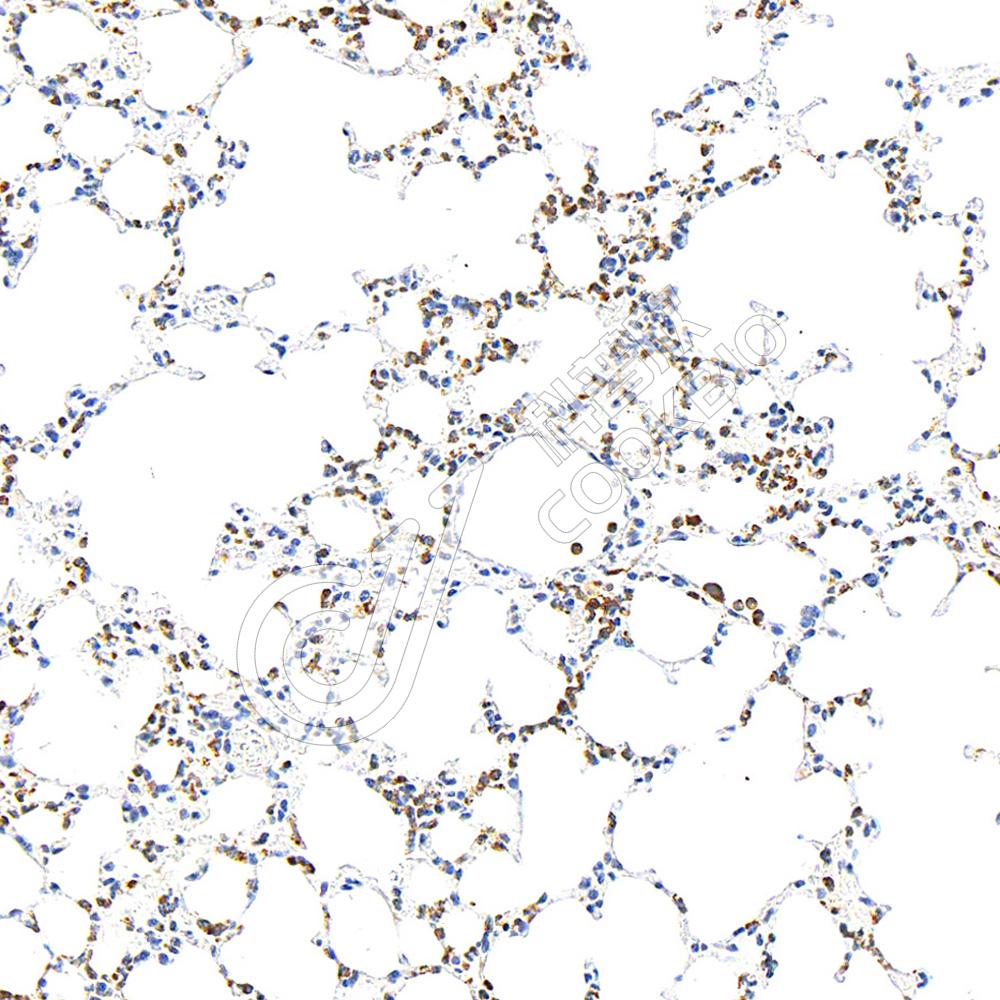

IHC检测Myeloperoxidase蛋白(货号 K2360048).

样品: 小鼠lps(24h)诱导肝脏炎症模型, 4%多聚甲醛 (货号KSG1101) 固定12-24小时.

抗原修复: 柠檬酸抗原修复液(干粉, pH 6.0) (KSG1201), 高压锅均匀喷气计时2分钟.

—抗: 1: 1000稀释, 4℃ 孵育过夜.

二抗: S-vision免疫组化多聚二抗(山羊抗小鼠), 即用型(货号KB3903), 室温孵育20分钟.